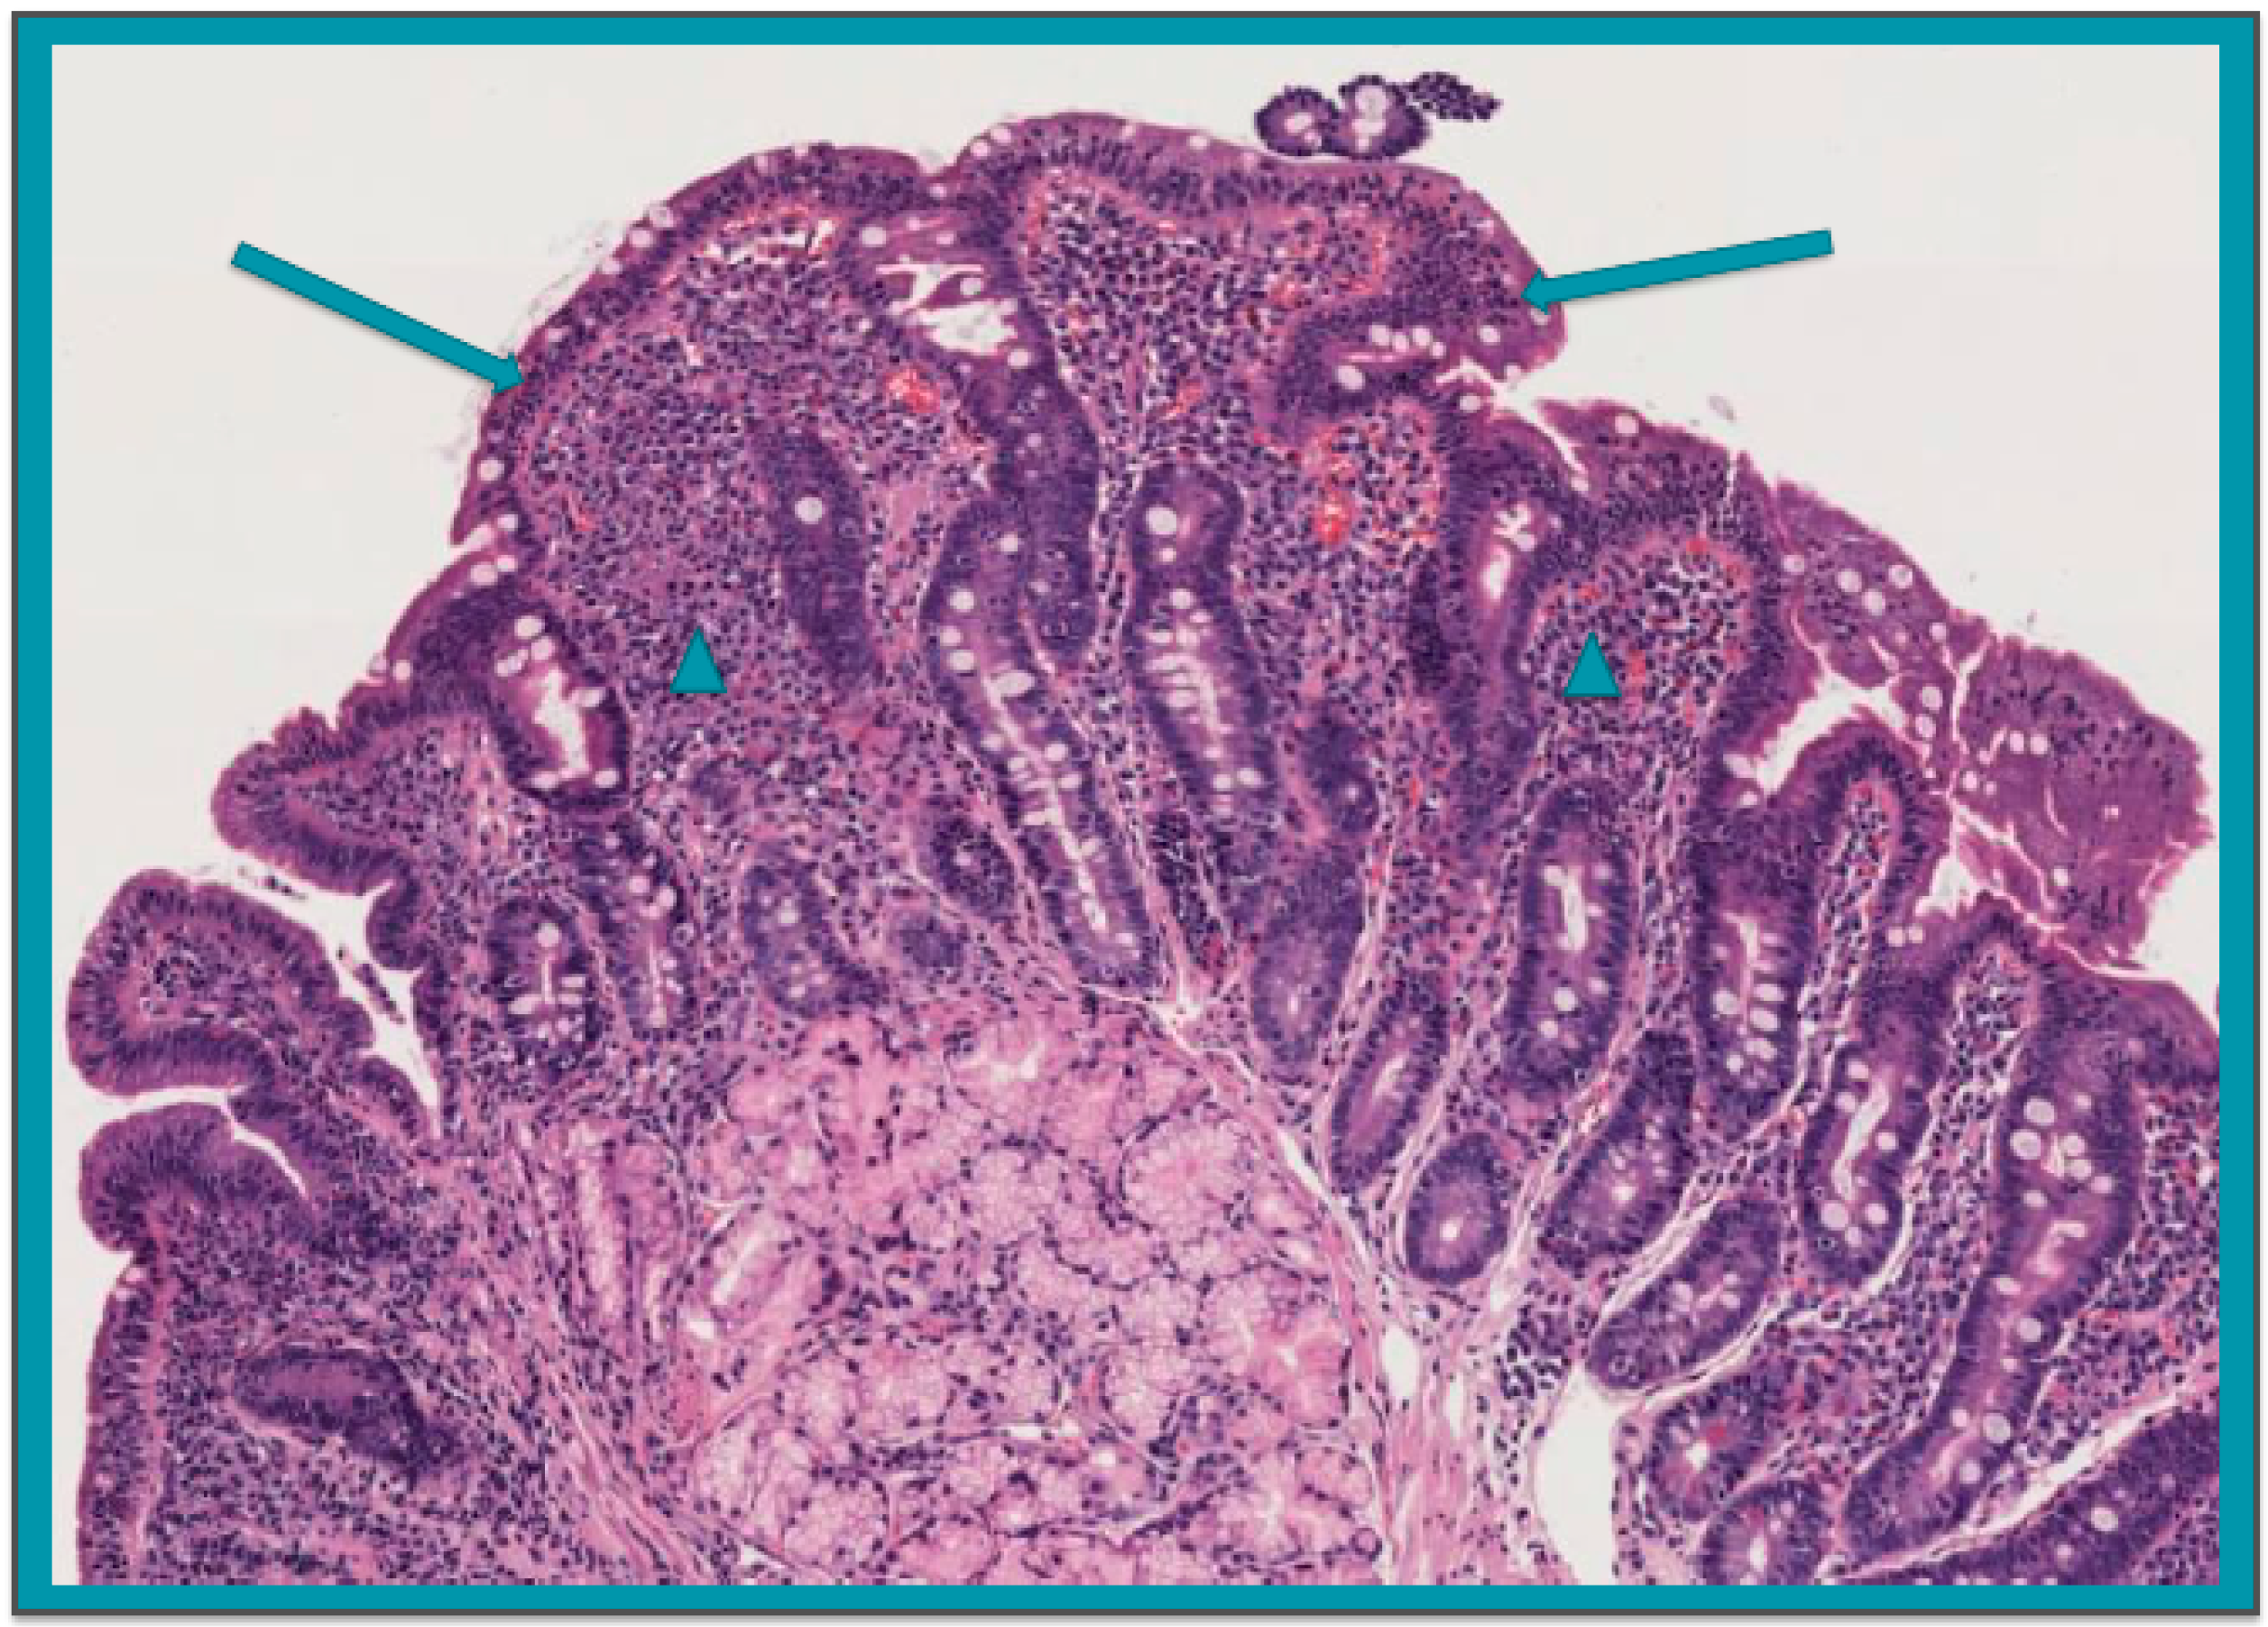

| Group 1 | 72 | 0 | 0 | 0 | Grade A lesions * | 1.4% (0.0–7.5) |

| Group 2 | 71 | 1 | 0 | 1 | Grade B1 lesions | 2.4% (0.0–7.6) |

| Group 3 | 32 | 0 | 0 | 0 | Not performed | 0% (0.0–10.9) |

| Group 4 | 92 | 1 + 2 borderline | 0 | 1 | Grade B2 lesions | 1.1% (0.0–5.9) |